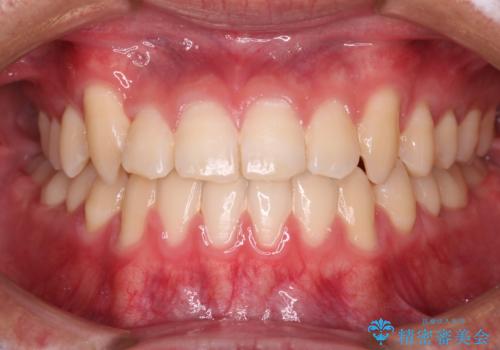

[ 奥歯の歯周病 ] エムドゲインを用いた再生治療